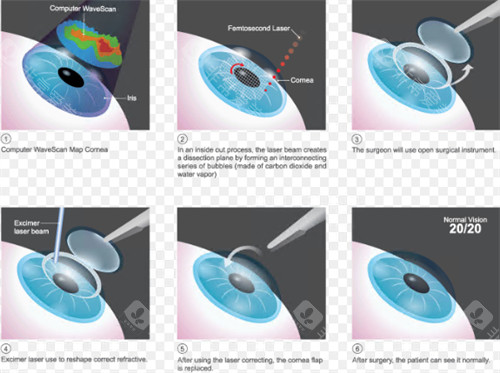

医院采用的手术方式主要有超声乳化白内障吸除术联合人工晶状体植入术等,这些手术方式具有切口小、改善快等优点。